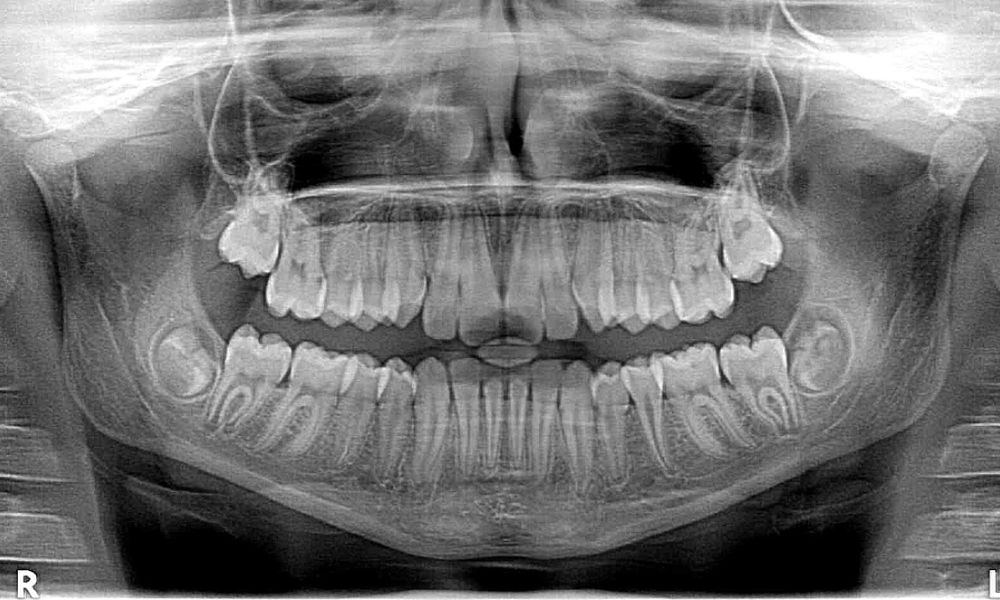

Dr. Andreas Seidel M.Sc.

Inhaber: Zahngesundheit Eichenau

Seit 2010: Zertifizierter Implantologe (DGI) und Endodontologe